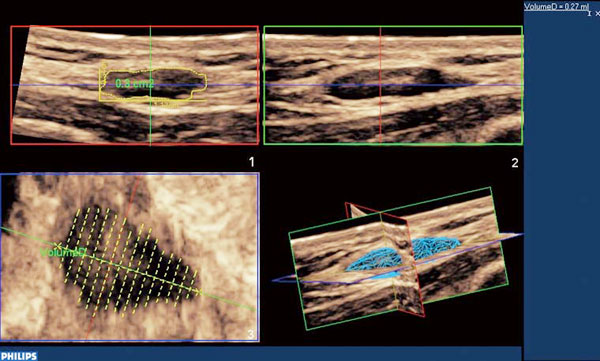

フィリップスは,心臓をはじめとする3D/4D技術に定評をいただいていますが,2009年後半に表在・血管向け3DプローブVL13-5をリリースしました。得られた3Dデータは前述のQLABにより,ボリュームデータを任意の方向から任意の感覚でスライスしたBモードを観察する,“i-Slice機能”を用いることで,読影診断のワークフローの向上を図ることが可能となります。また自動/半自動トレースによる容量計測機能により,腫瘍の容量評価も可能にします。

図1 QLABによる容量計測